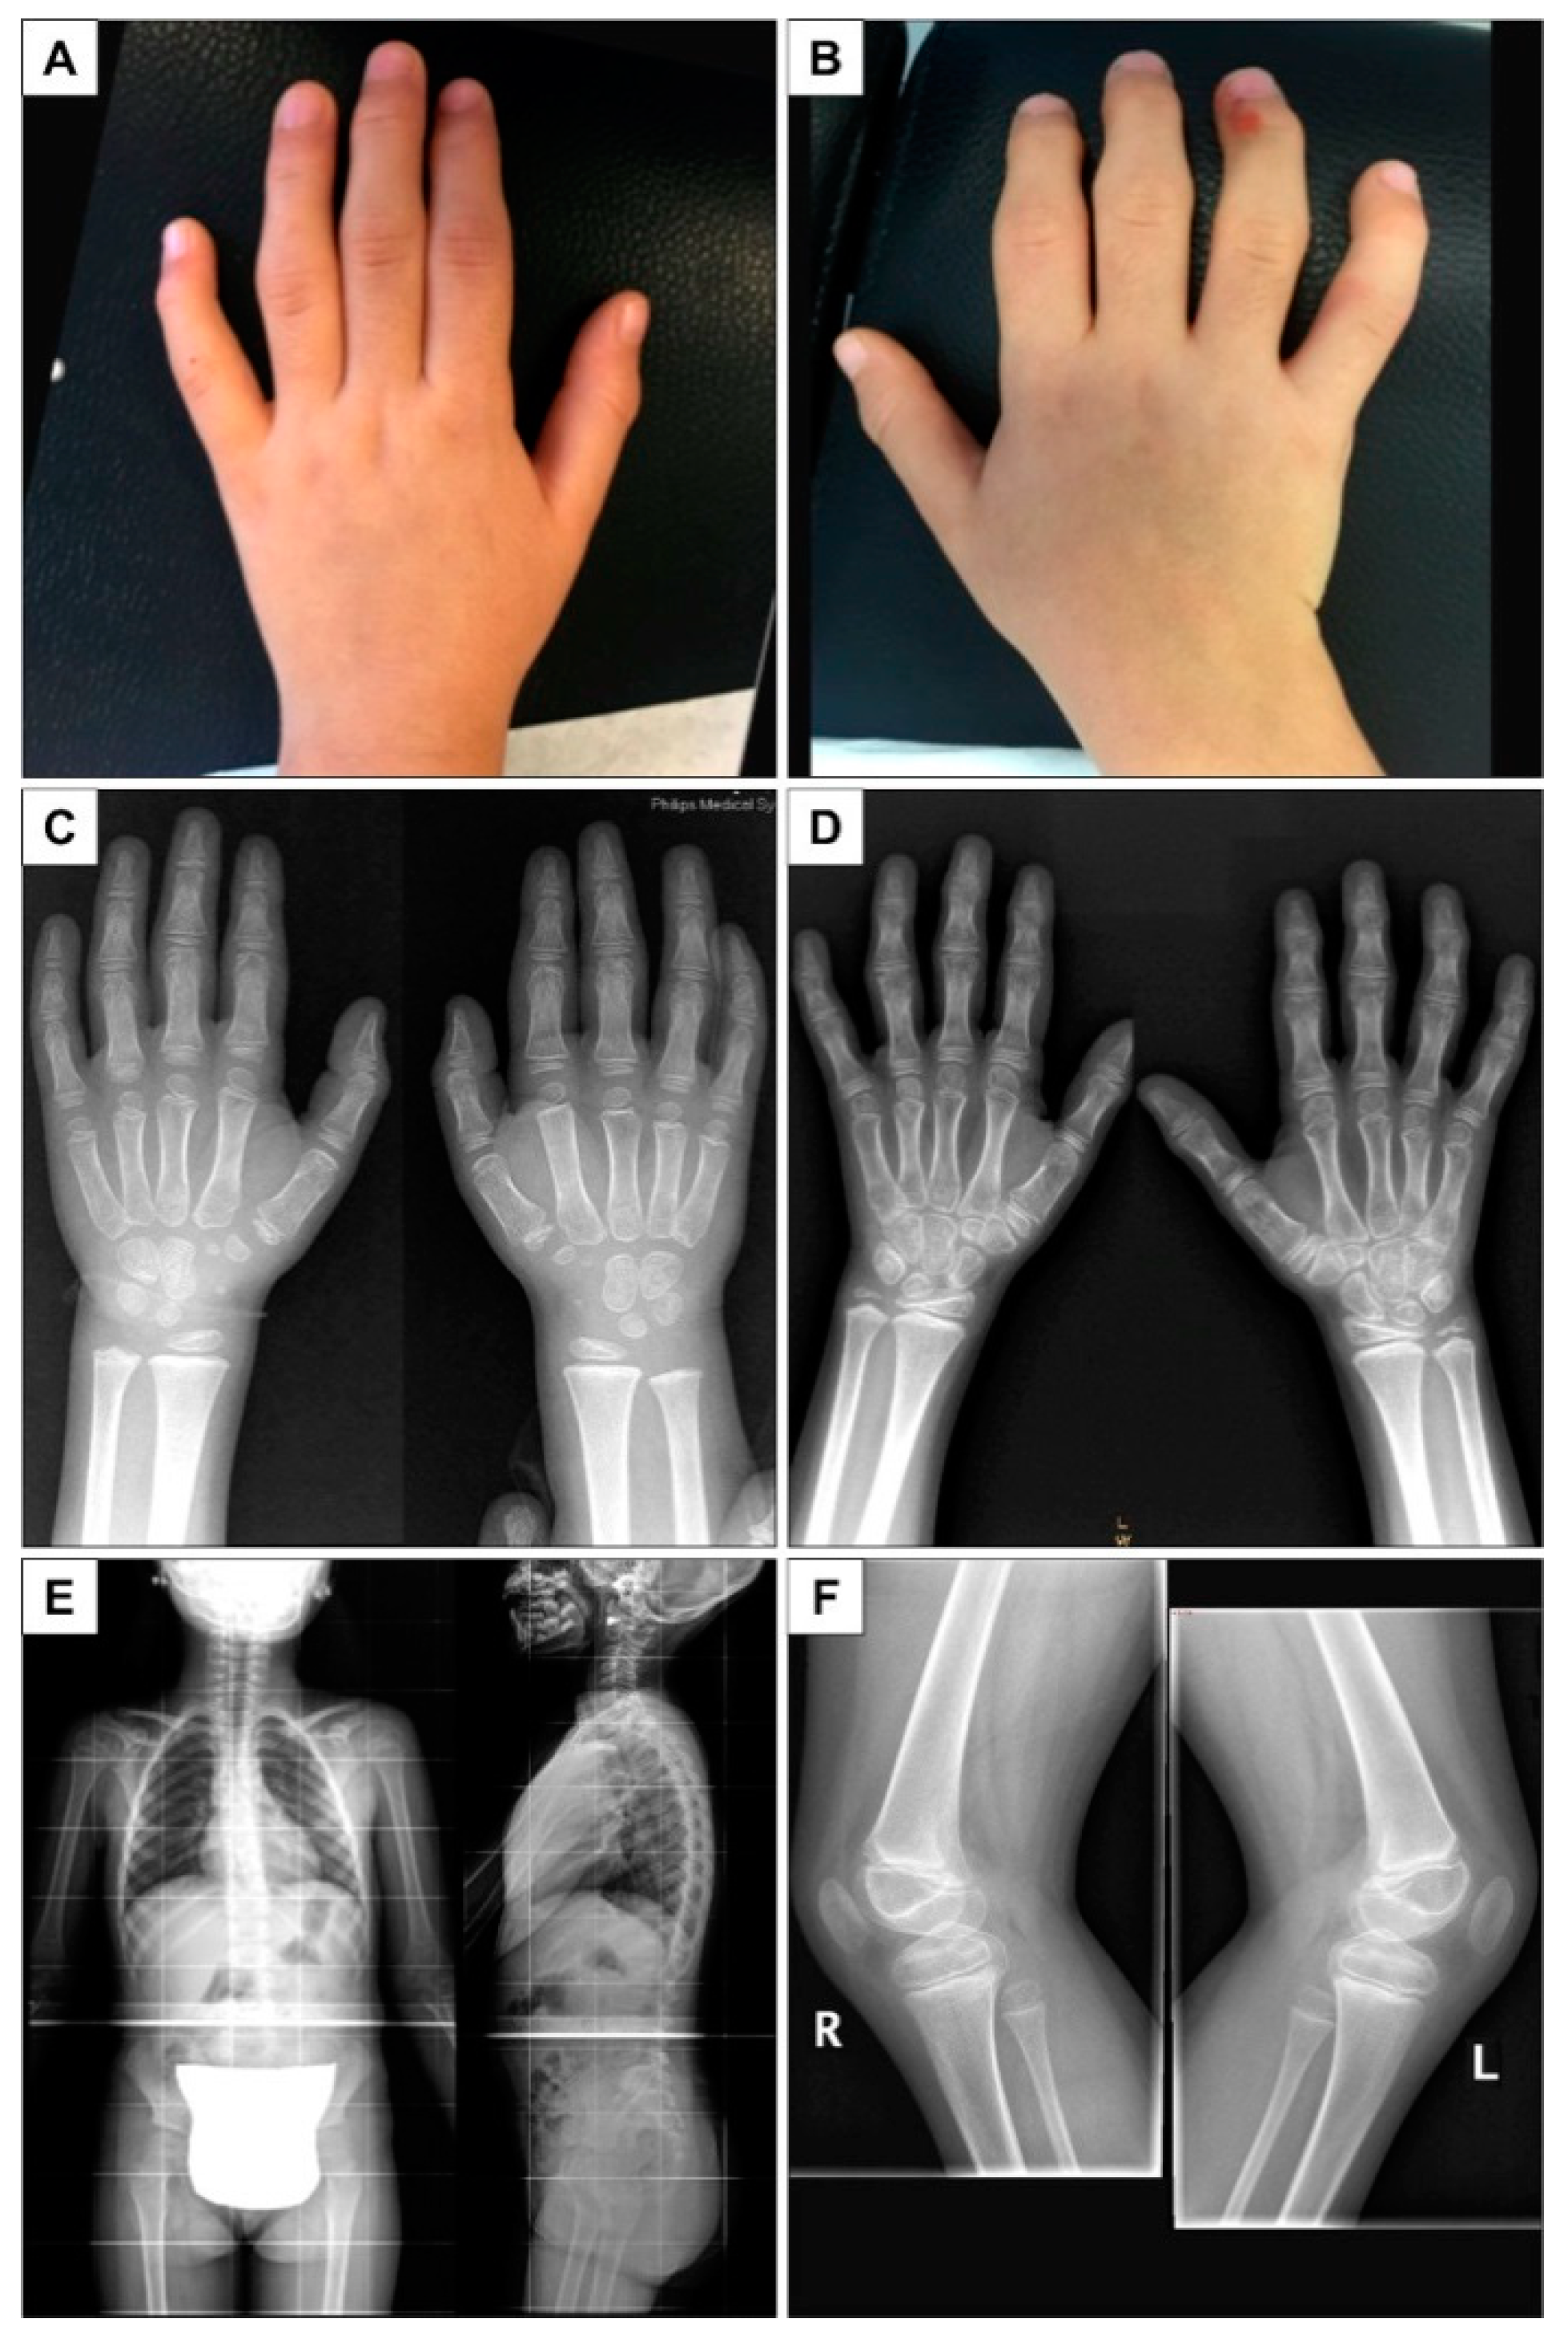

2. Case Presentation

| Inter-Phalangeal Deformity | Yes | Yes |